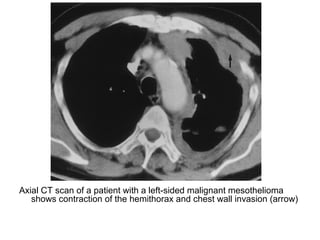

Axial CT scan of a patient with a left-sided malignant mesothelioma

shows contraction of the hemithorax and chest wall invasion (arrow)